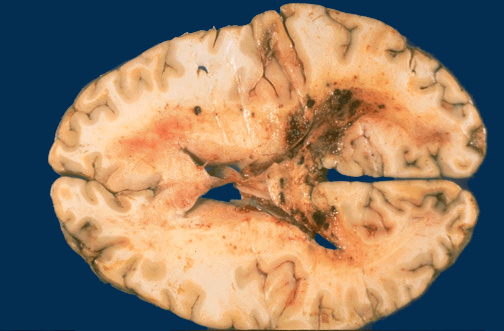

Image 6.3

This is a gross photograph of a similar lesion from an elderly man who died.